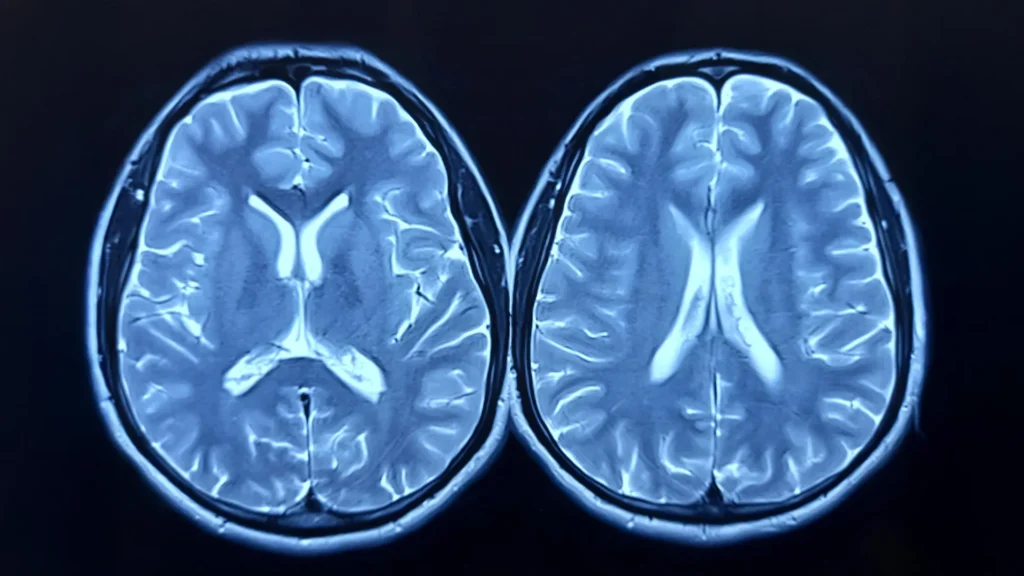

The research team looked at longitudinal brain scans from nearly 1,000 healthy adults, taken as part of the UK Biobank study. Some participants had scans before and after the pandemic; others, only before. Using advanced imaging and machine learning, the researchers estimated each person’s “brain age” — how old their brain appeared to be compared to their actual age.

The brain age model was developed using brain scans from over 15,000 healthy individuals, without comorbidities, allowing the researchers to build an accurate model for estimating brain age.